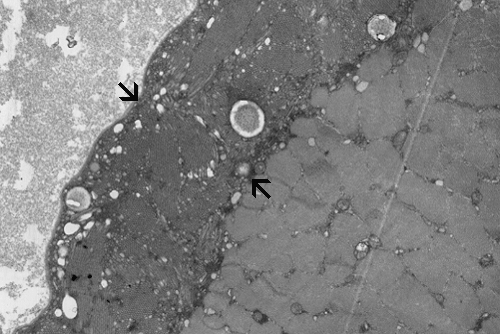

Pathology of the case: On hematoxylin-eosin stained frozen sections, there are many stongly basophilic, irregular subsarcolemmal depositions (Panel A and B). There is no significant variation in fiber diameter, increase in centrally located nucleus, inflammation, necrotic fiber, regenerating fibers or target fibers. These deposits appear bright red on modified Gomori's trichrome (Panel C). On ATPase reaction at pH 4.6 (dark fibers are type 1, pale fibers are type 2a while intermediate-intensity fibers are type 2b), there is no fiber type predominance (Panel D). Although the deposits are not visualized in the ATPase preparation, they are strongly reactive in NADH-TR reaction. Intesestingly, these deposits are not visualized in another preparation of oxidative enzyme- succinate dehydrogenase (Panel F). On the adenylate deaminase preparation, these deposits are strongly reactive (Panel G). The subsarcolemmal deposits are well visualized under the electron microscope which is electron dense (Panel H). On cross sections, these deposits are bundles of densely packed polygonal to round tubules with double walls that are arranged in small fascicles (Panel  I and J). The tubules are about 50-80 nm in diameter. The tubular aggregates also arrange in longitudinal bundles that run along the myofibrils (Panel K).

On resin embedded semithin sections, tubular aggregates may measure over 40 mm in length on longitudinal sections. At the ultrastructural level, tubular aggregates appear as masses of bundles of long, straight, parallel tubules in between myofibrils especially beneath subsarcolemmal locations. They are often double barrel and contains an inner tube but they may be up to eight inner tubes. The outer tube is usually about 50 nm in diameter but may be as large as 80 nm. The inner tubules are 20-30 nm in diameter.